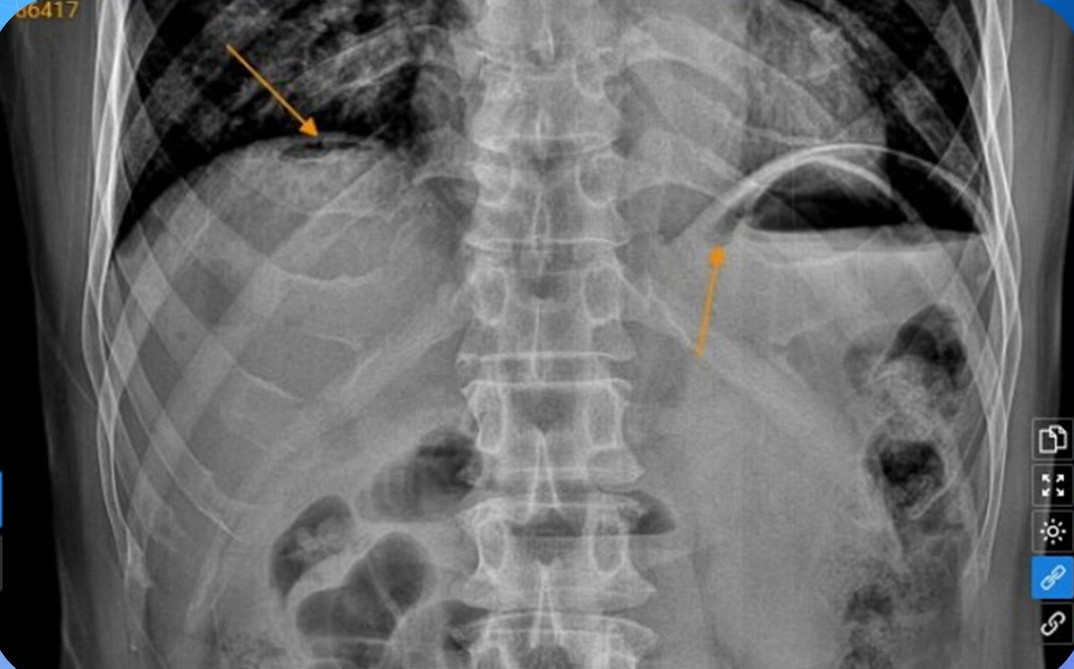

Bệnh nhân được chỉ định một số xét nghiệm cận lâm sàng, chẩn đoán hình ảnh phục vụ chẩn đoán. Kết quả xét nghiệm máu trong giới hạn bình thường, đặc biệt chụp X-quang ổ bụng không chuẩn bị phát hiện hình ảnh liềm hơi dưới vòm hoành 2 bên và hình ảnh siêu âm ổ bụng tổng quát cho thấy dấu hiệu rèm cửa vùng thượng vị. Đây là hai dấu hiệu kinh điển trong trường hợp thủng tạng rỗng.

| Chụp X-quang phát hiện bệnh nhân thủng tạng. Ảnh BVCC |